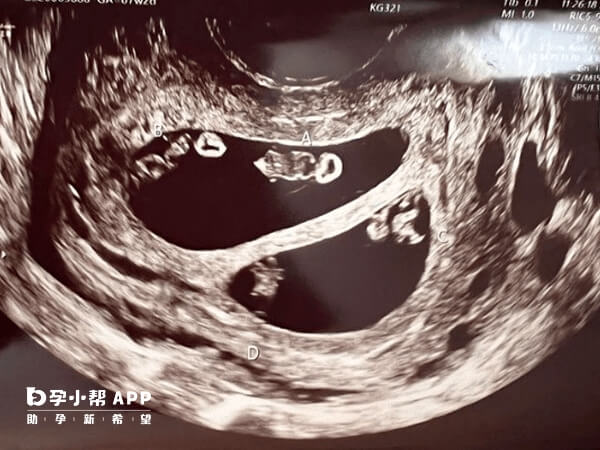

通过试管婴儿技术实现龙凤胎需要满足一定条件,比如女性年龄一般建议在35岁以下,子宫内膜厚度≥8mm,子宫形态正常且无肌瘤、粘连等问题,以及有足够数量的优质胚胎等,这样才能提高生育龙凤胎的几率,毕竟龙凤胎属于双胞胎的一种,可能会带来早产、妊娠期并发症等高危妊娠风险。

数量较多。胚胎经过体外受精和胚胎培养的过程中,会把卵子和精子培育成为胚胎,而胚胎的数量和质量与卵子和精子的质量有关,如果质量都比较好,那么胚胎数量也比较多,质量也更好,所以在移植到子宫腔以后,能够顺利着床。

子宫环境是胚胎着床发育的场所,尤其是内膜的容受性更是决定了胚胎的着床率,因此要调理好子宫环境。对于一些可能影响胚胎着床的因素,比如子宫肌瘤、子宫内膜息肉、输卵管积水等等,都需要提前处理。

这也是双胎妊娠的重要条件,因为只有身体情况适合妊娠双胎,医生才会种植2个胚胎,而2个胚胎在子宫环境好,胚胎质量好的前提下,着床率也会提高,所以双胎妊娠的几率也就更大一些。但如果是本身不适合双胎妊娠的患者,医生会选择性的移植单胚,降低多胎率。

综合现有数据和研究了解,若移植两个胚胎,试管婴儿双胞胎妊娠几率约为20%-30%,其中龙凤胎的概率约占双胞胎的1/3左右(即约7%-10%)。若移植三个胚胎,多胎妊娠几率可能升至30%-40%,但龙凤胎概率需结合具体胚胎组合情况判断。